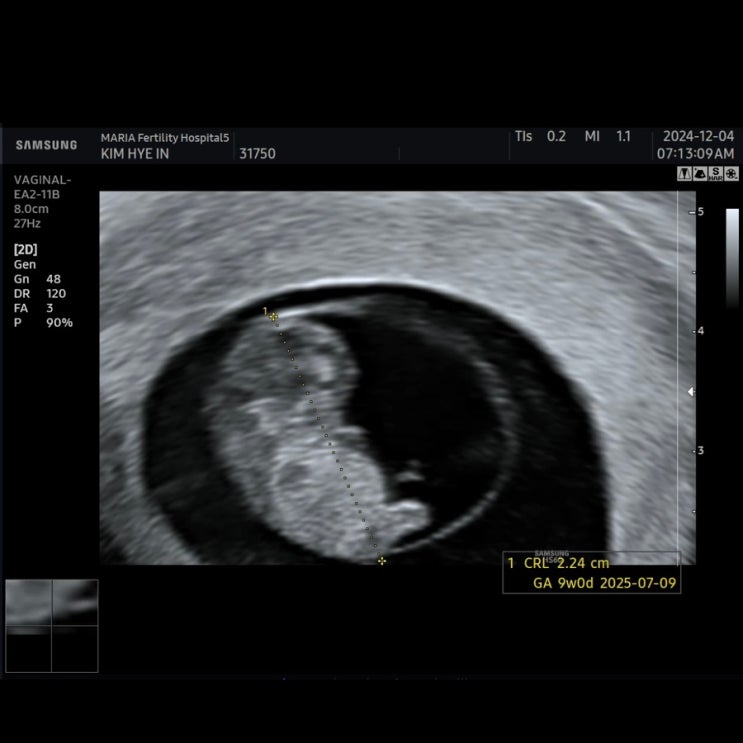

임신 9주차 / 마리아 졸업, 체함, 도파민 충전 완료!

9주 0일 ∨ 짧게짧게 꿈을 많이 꿈 ∨ 화장실은 여전히 ing ∨ 오랜만에 체해서 너무 힘들었다... ∨ 과일,...